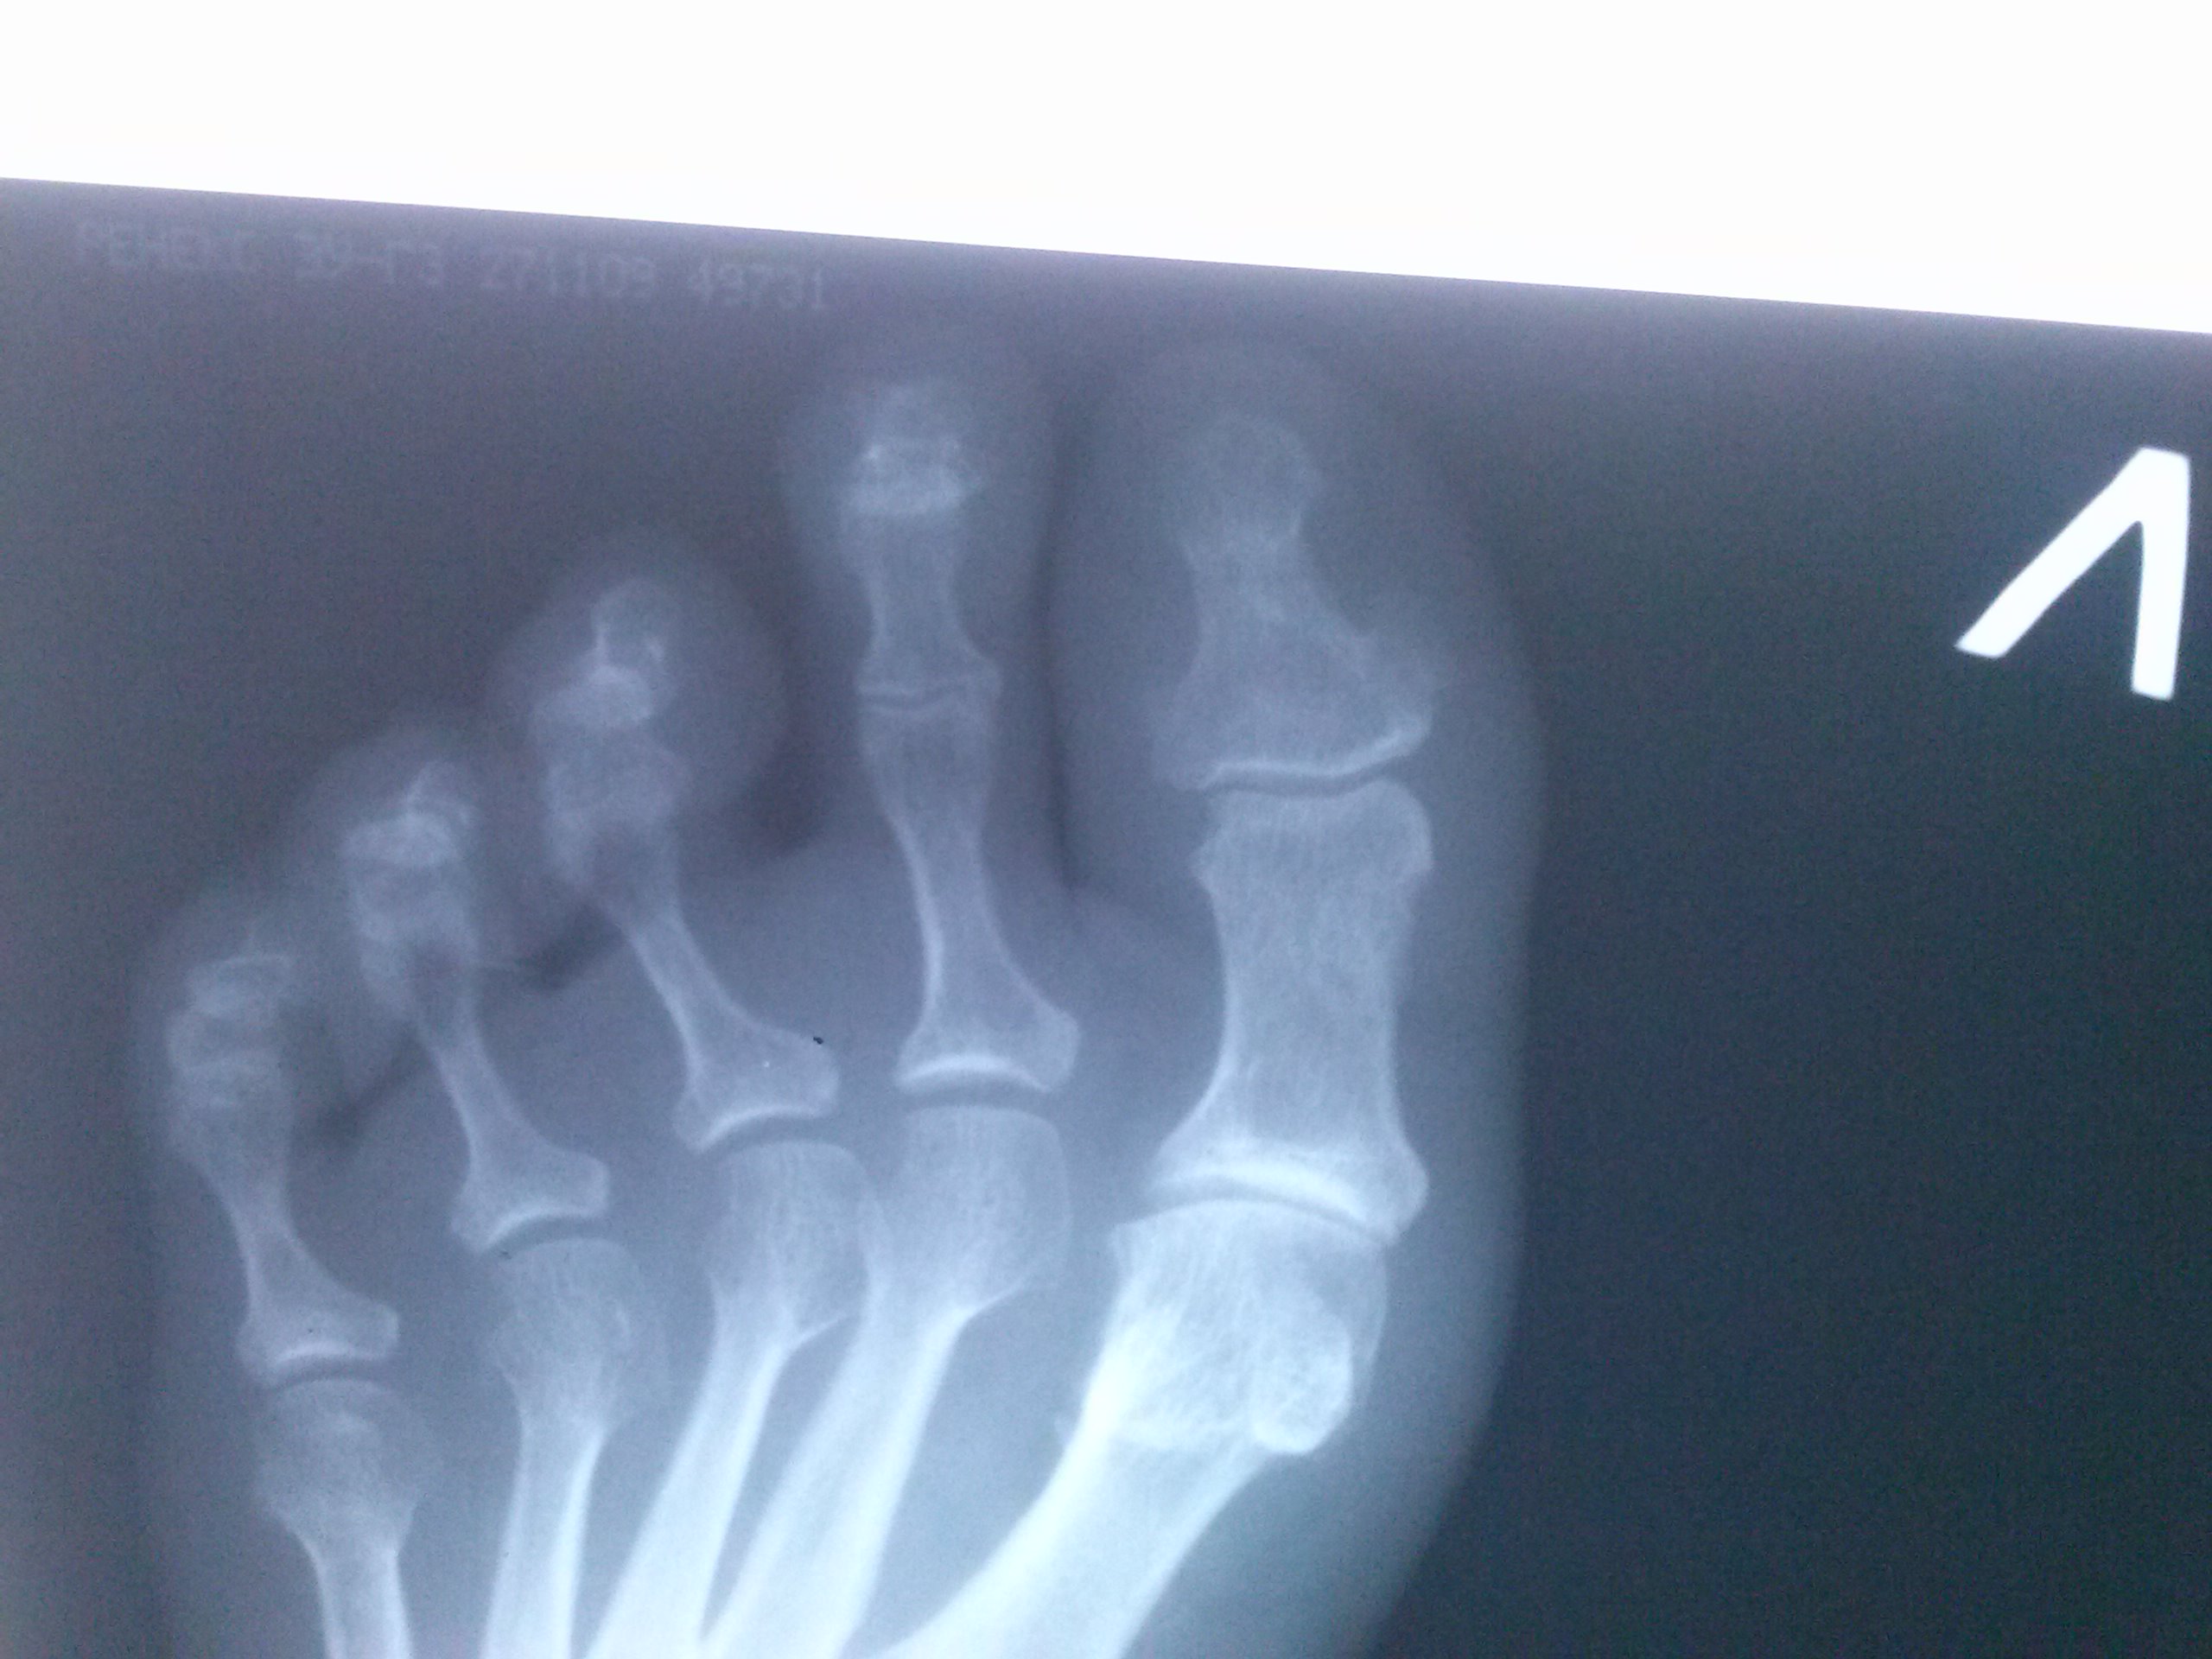

женщина 1957 г.р. жалобы на ноющие боли по утрам в суставах кистей рук (считает себя больной больше месяца). Терапевт ставит под вопросом ревматомдный артрит. А может здесь подагра? по моему для...

Тип: Клиническое наблюдение

Область: Скелетно-мышечная система

Модальность: Rg

Дата: 12.07.2010 - 09:00